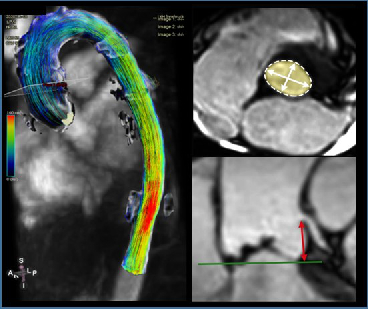

Cardiovascular MR Imaging

Agnes Mayr, Christian Kremser, in cooperation with the Department of Cardiology

a) STEMI CMR: CMR Parameters of Myocardial Tissue Damage in ST-Elevation Myocardial Infarction (STEMI).

Since 2005, almost 900 patients have been examined under a comprehensive cardiac MRI (CMR) protocol within the first week as well as 4 months, 12 months and 10 years after acute STEMI. In more than 60 internal original papers, CMR myocardial infarction severity markers were assessed and the effects of CMR on optimised risk assessment shortly after STEMI were evaluated.

b) TAVI CMR: CMR to Guide Transcatheter Aortic Valve Implantation (TAVI).

This ongoing randomised study investigates the non-inferiority of TAVI CMR to TAVI CT for the first time, with regard to efficacy and safety end-points in the guidance for TAVI evaluation.

c) 4D Phase Contrast Flow Measurements

- Patients with different grades of aortic valve stenosis: comparison of 4D flow-assessed stenosis severity with 3D echocardiography and invasive measurements.

- Patients with cryptogenic stroke: recording turbulent kinetic energy, changes in flow patterns and regional wall stresses as well as occurrence of a vortex-shaped flow along the thoracic aortic wall, in order to optimise the elucidation of potential cardioembolic sources.